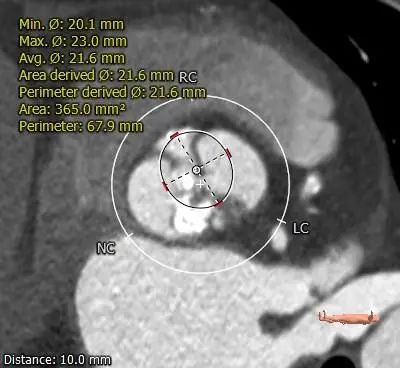

ANNULUS

2mm SUPRA ANNULUS

4mm SUPRA ANNULUS

6mm SUPRA ANNULUS

8mm SUPRA ANNULUS

10mm SUPRA ANNULUS

12mm SUPRA ANNULUS